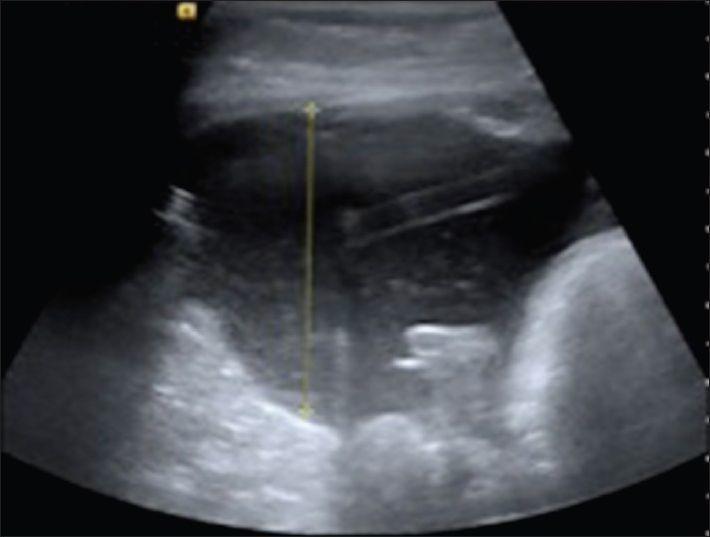

A 1-year-old girl with craniopharyngioma required external drainage of 40-50 mL/h of cerebrospinal fluid (CSF) after biopsy and cyst fenestration. She developed CSF ascites following insertion of a ventriculoperitoneal (VP) shunt and a distended painful gallbladder following ventriculogallbladder shunt insertion. Revision to a ventriculoatrial shunt was required. This is the first time a craniopharyngioma has been reported to cause increased CSF production. The potential mechanisms of CSF overproduction and the difficulties managing the large volume of CSF in a young child are discussed.

一名1岁患颅咽管瘤的女孩在活检和囊肿开窗术后需要每小时引流40 - 50毫升脑脊液。她在插入脑室腹腔(VP)分流管后出现脑脊液腹水,在插入脑室胆囊分流管后出现胆囊扩张疼痛。需要将分流管改为脑室心房分流管。这是首次报道颅咽管瘤导致脑脊液生成增加。本文讨论了脑脊液过度生成的潜在机制以及在幼儿中处理大量脑脊液的困难。